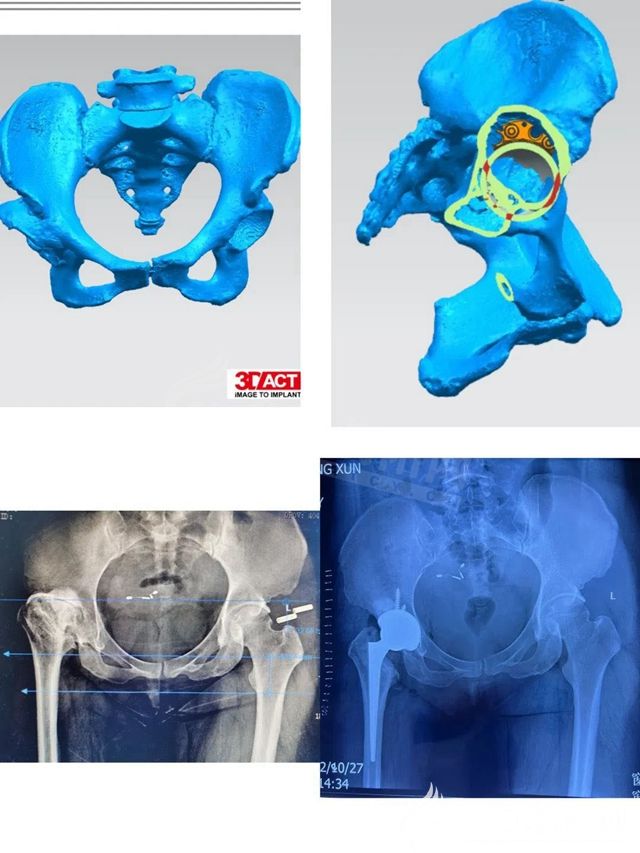

數(shù)字化骨科技術(shù)運(yùn)用3D打印技術(shù)把患者的患病部位用多排CT術(shù)前掃描重建,然后根據(jù)數(shù)據(jù)用3D打印機(jī)打印出患者的病變部位,根據(jù)數(shù)字模型制作或準(zhǔn)備與之匹配的關(guān)節(jié)假體和配套的手術(shù)器械,再進(jìn)行手術(shù),以便減少手術(shù)創(chuàng)傷,使手術(shù)更加精準(zhǔn),手術(shù)質(zhì)量更有保障。而這個(gè)手術(shù)的難點(diǎn)就在于病人髖臼骨量缺損,股骨端畸形,周圍軟組織攣縮,術(shù)中還需要矯正雙下肢不等長(zhǎng),軟組織不平衡會(huì)導(dǎo)致術(shù)后脫位。

術(shù)前,趙新潔與骨傷一科主治醫(yī)生張愛(ài)東對(duì)患者進(jìn)行了認(rèn)真細(xì)致的檢查,組織科內(nèi)全體醫(yī)生進(jìn)行會(huì)診討論,制定了嚴(yán)密的手術(shù)計(jì)劃。在麻醉科主任李鵬和醫(yī)生劉冬梅的協(xié)助下,手術(shù)近3個(gè)小時(shí),矯正了雙下肢不等長(zhǎng),獲得成功。